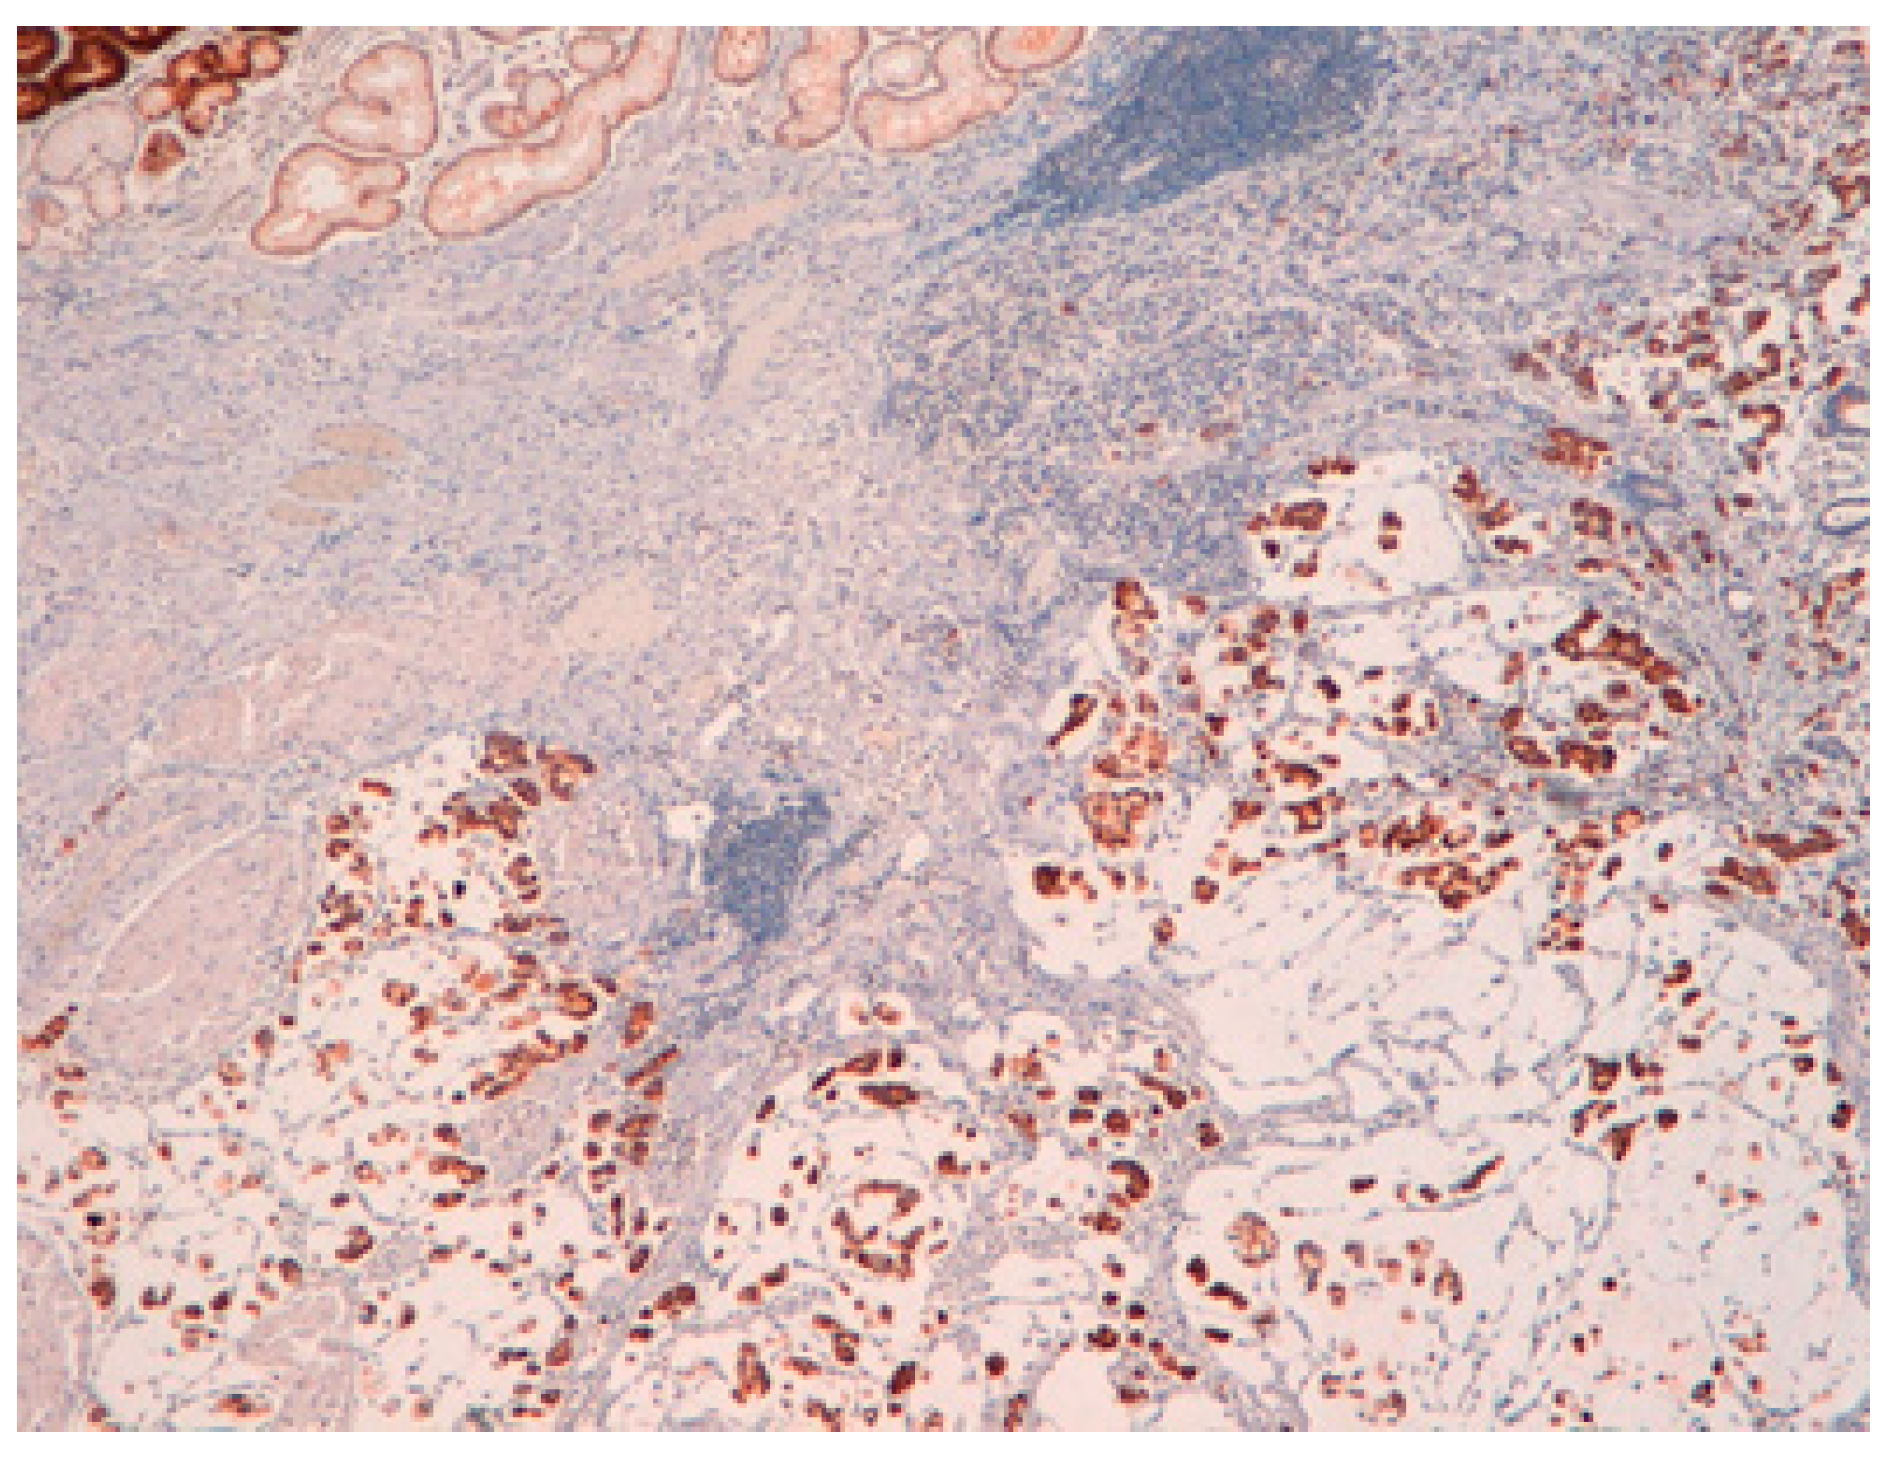

4. Intestinal Metaplasia

- Reis, C.A.; David, L.; Correa, P.; Carneiro, F.; de Bolós, C.; Garcia, E.; Mandel, U.; Clausen, H.; Sobrinho-Simões, M. Intestinal metaplasia of human stomach displays distinct patterns of mucin (MUC1, MUC2, MUC5AC, and MUC6) expression. Cancer Res. 1999, 59, 1003–1007. [Google Scholar] [PubMed]

- Silva, E.; Teixeira, A.; David, L.; Carneiro, F.; Reis, C.A.; Sobrinho-Simões, J.; Serpa, J.; Veerman, E.; Bolscher, J.; Sobrinho-Simões, M. Mucins as key molecules for the classification of intestinal metaplasia of the stomach. Virchows Arch. 2002, 440, 311–317. [Google Scholar] [CrossRef] [PubMed]